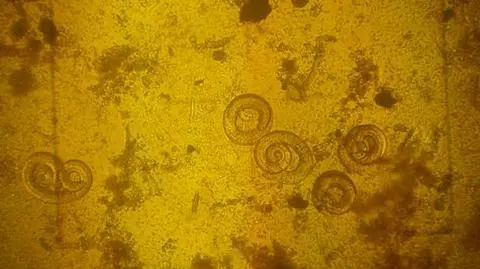

Spirale Trichinelli

W taki sposób dochodzi do zakażenia mózgu człowieka przez amebę